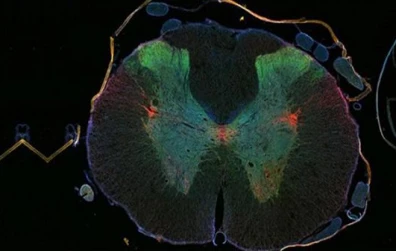

Dr. Nancy Bonini, a professor at the University of Pennsylvania, and his colleague Dr. James Shorter led a study that found that in addition to preventing tumor cells from repairing damaged DNA, PARP inhibitors can also reduce amyotrophic lateral sclerosis (ALS). It is known as the formation of Lou Gehrig's disease-related structures, as well as some forms of frontotemporal degeneration (FTD).

TDP-43 is a member of the heteronuclear nuclear ribonucleoprotein (hnRNP) protein family, affecting pre-mRNA splicing, transcription, mRNA stability and mRNA transport. In ALS and FTD, hyperphosphorylated TDP-43 protein molecules are in the cytoplasm and can co-locate with parts of the "stress granule". However, the specific mechanism of TDP-43 pathological aggregation into the nucleus remains unknown.

Scientists have found that in Drosophila, a PARP called tankyrase is down-regulated, which reduces the accumulation of TDP-43 in the cytoplasm and effectively reduces neurodegeneration. It was further determined that TDP-43 binds PAR non-covalently by intercalating the PAR binding sequence region within its nuclear localization sequence.

Experiments have shown that PAR binding promotes liquid phase separation of TDP-43 and demonstrates in mammalian cell and neuronal cell assays that this binding is a prerequisite for the accumulation of TDP-43 in stress granules. Targeting stress particles initially protects TDP-43 from disease-associated phosphorylation, but in long-term stress, stress particles dissociate, leaving phosphorylated TDP-43 aggregates.

Further experiments in cultured mammalian cells demonstrated that the PARP inhibitor, a small molecule of Tankyrase-1/2, inhibited the formation of only TDP-43 hyperphosphorylated aggregates in the cytoplasm without affecting the assembly of stress particles. Tankyrase inhibitors antagonize the pathological progression and neurodegeneration associated with TDP-43 and may therefore have therapeutic utility for ALS and FTD.